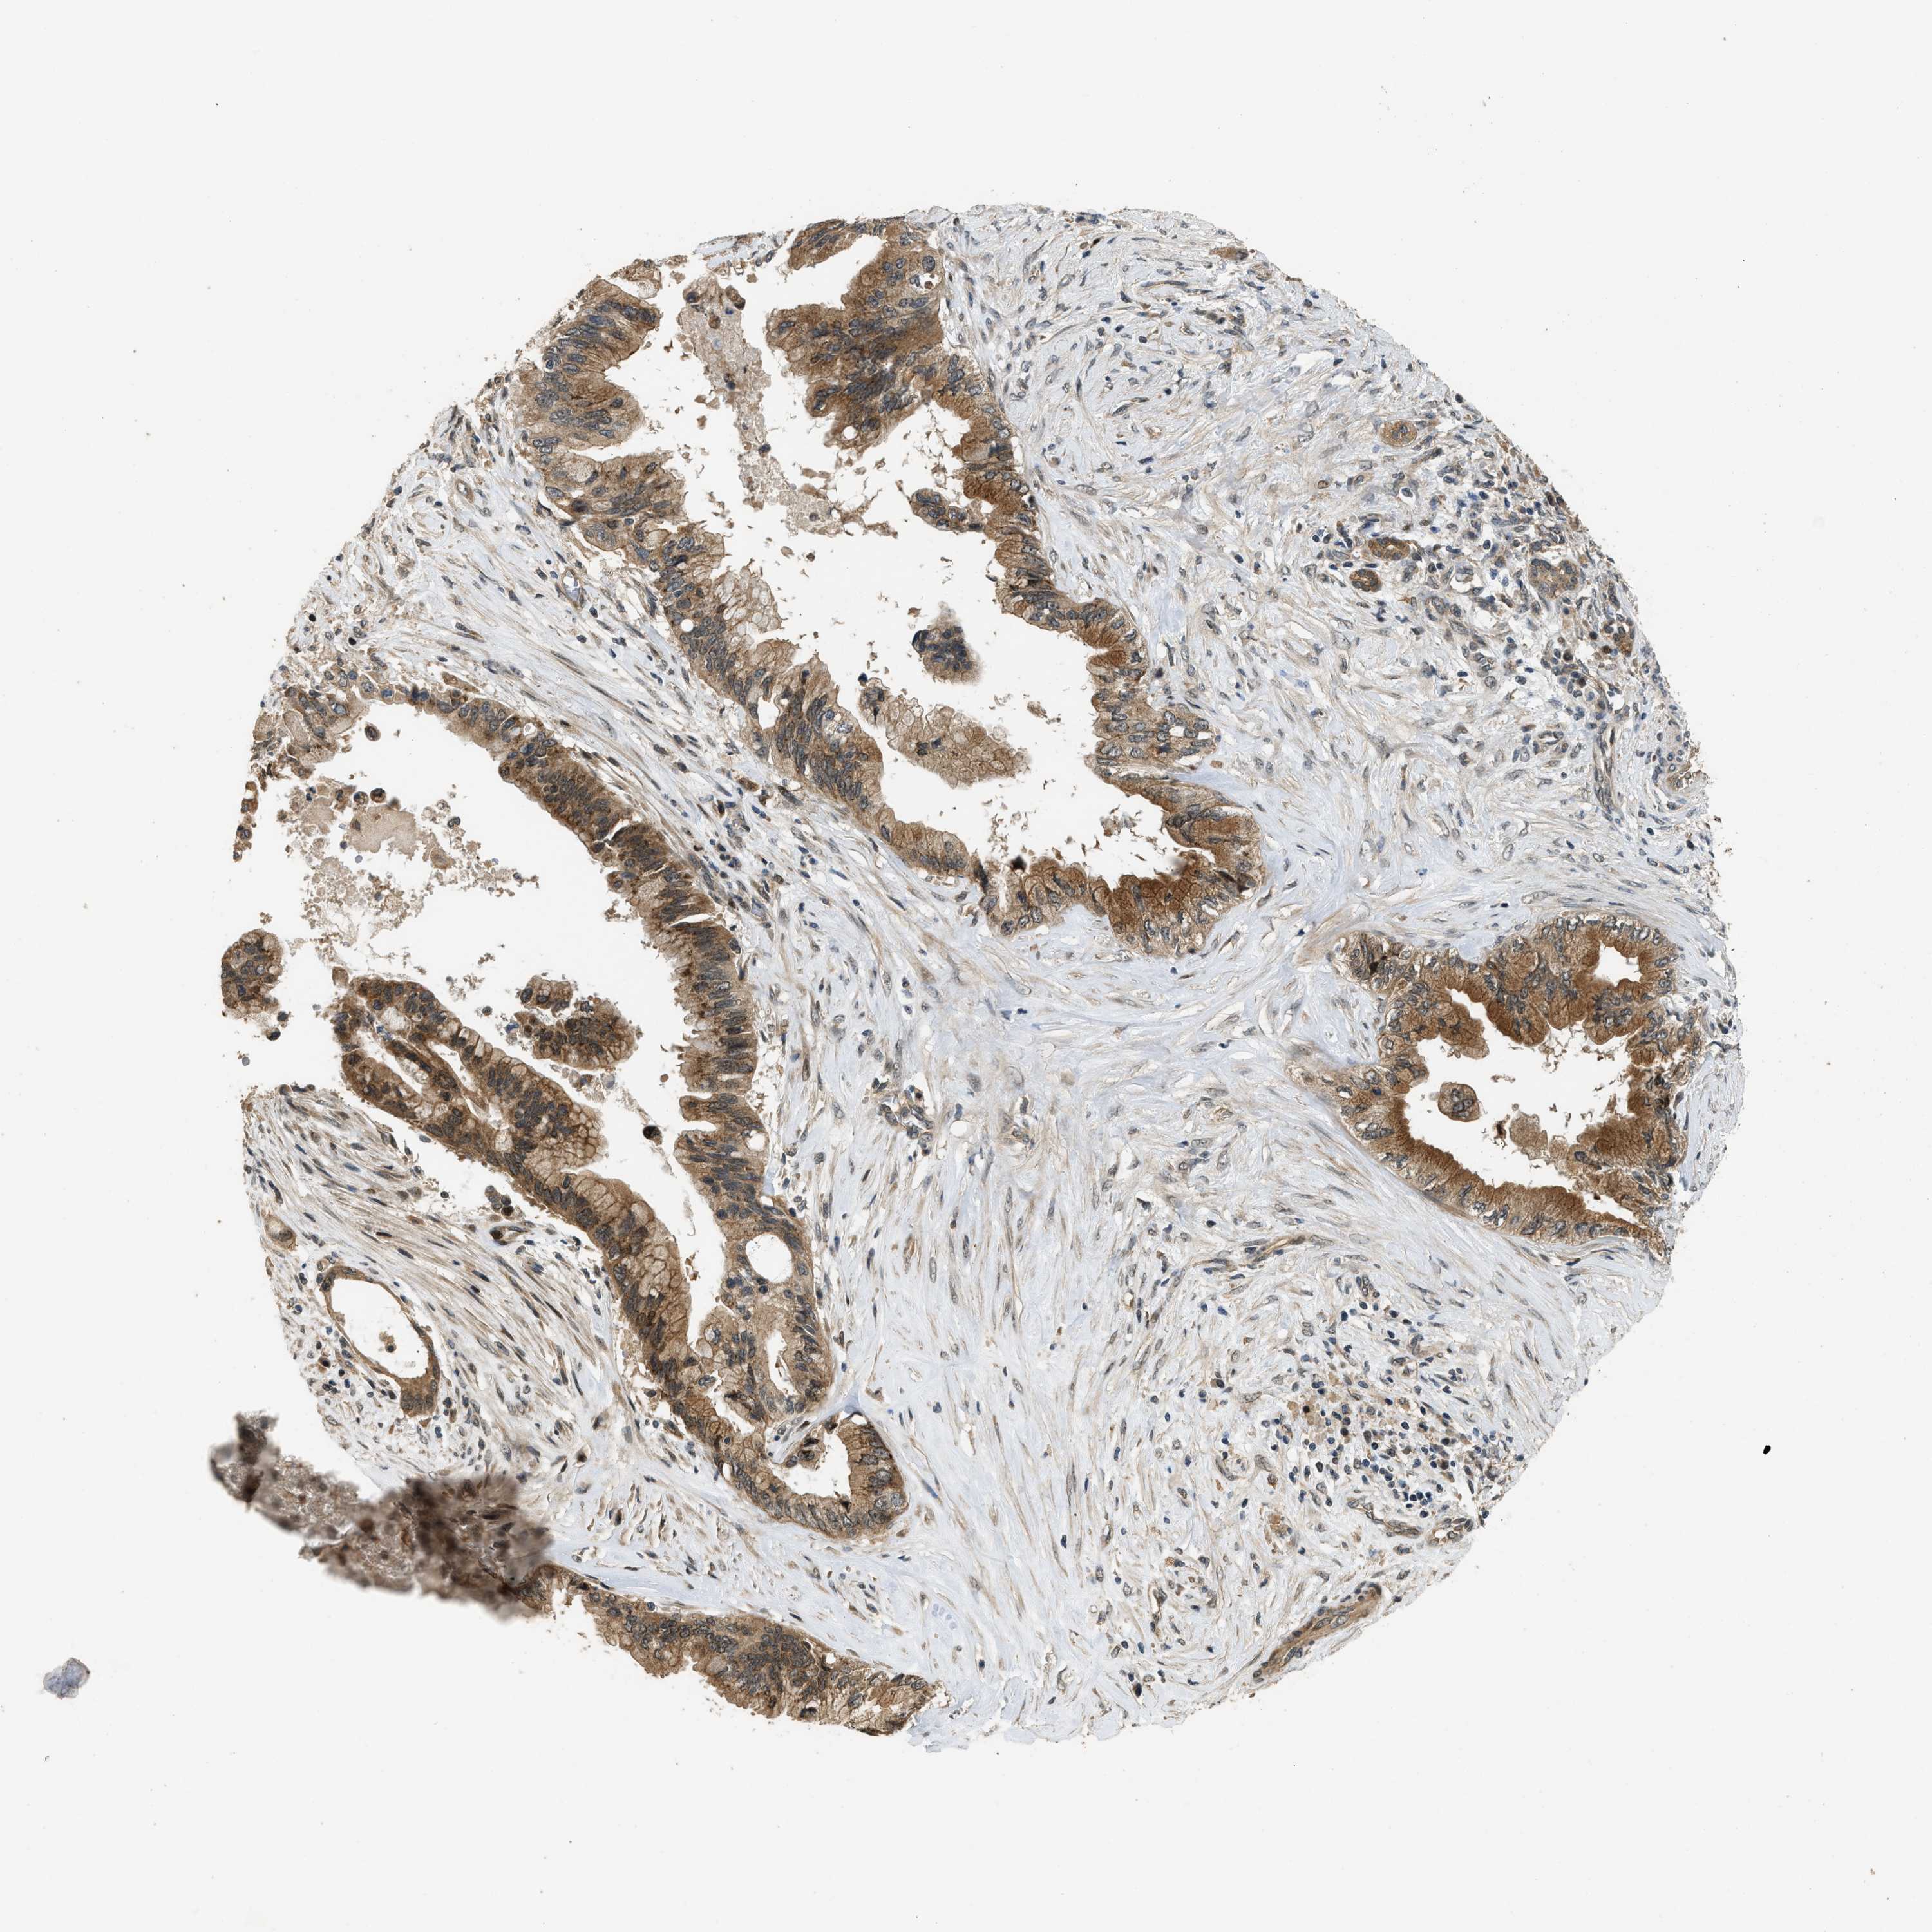

PANCREATIC CANCER - Protein expressioni

A mouse-over function shows sample information and annotation data. Click on an image to view it in a full screen mode. Samples can be filtered based on level of antibody staining by selecting one or several of the following categories: high, medium, low and not detected. The assay and annotation is described here.

Note that samples used for immunohistochemistry by the Human Protein Atlas do not correspond to samples in the TCGA dataset.

Antibody stainingi

Antibody staining in the annotated cell types in the current human tissue is reported as not detected, low, medium, or high, based on conventional immunohistochemistry profiling in selected tissues. This score is based on the combination of the staining intensity and fraction of stained cells.

Each image is clickable and will lead to virtual microscopy that enables deeper exploration of all samples and also displays staining intensity scores, fraction scores and subcellular localization as well as patient and tissue information for each sample.

Antibody HPA018527

Staining

High

Medium

Low

Not detected

Intensity

Strong

Moderate

Weak

Negative

Quantity

>75%

75%-25%

<25%

None

Location

Nuclear

Cytoplasmic/membranous

Cytoplasmic/membranous,nuclear

Adenocarcinoma, NOS